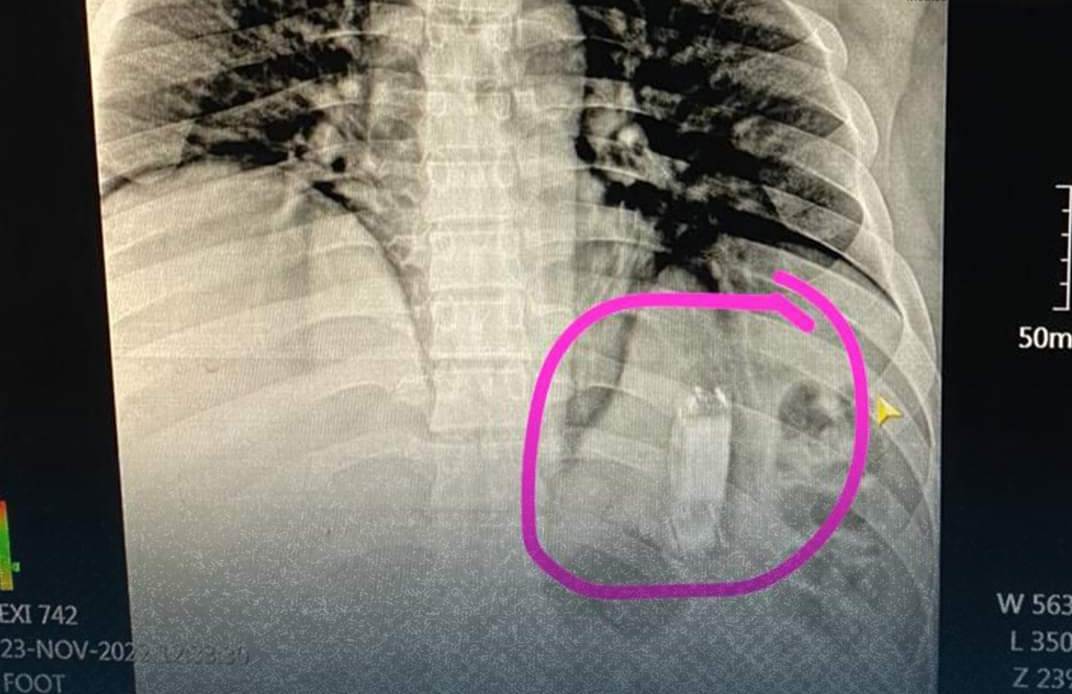

حيث استقبل المستشفى شاب يبلغ 40 عامًا، يعاني من آلام في المعدة وقيء، وبإجراء الكشف الطبي عليه وعمل الأشعات والفحوصات الطبية اللازمة، تبين وجود جسم غريب داخل المعدة.

وتمكن أطباء وحدة مناظير الكبد الجهاز الهضمي بالمستشفى، من استخراج الجسم باستخدام منظار المعدة والمرئ، وتبين أنه هاتف محمول ابتلعه المريض.